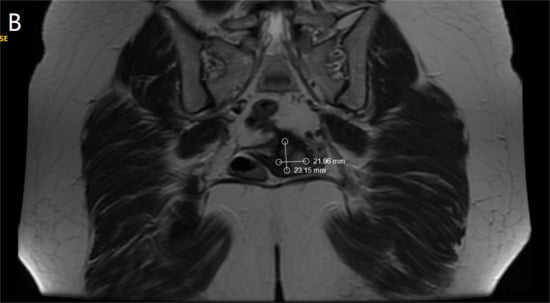

Ultrasound examination of the abdomen and pelvis revealed no abnormal findings, and lung radiography was normal. Preoperative magnetic resonance imaging (MRI) identified an infiltrative tumor measuring 23.69 × 21.70 mm, as demonstrated in Figure 1A,B.

Figure 1.

(A). MRI—Sagittal section of the tumor formation (B). MRI—Coronal section of the tumor formation.